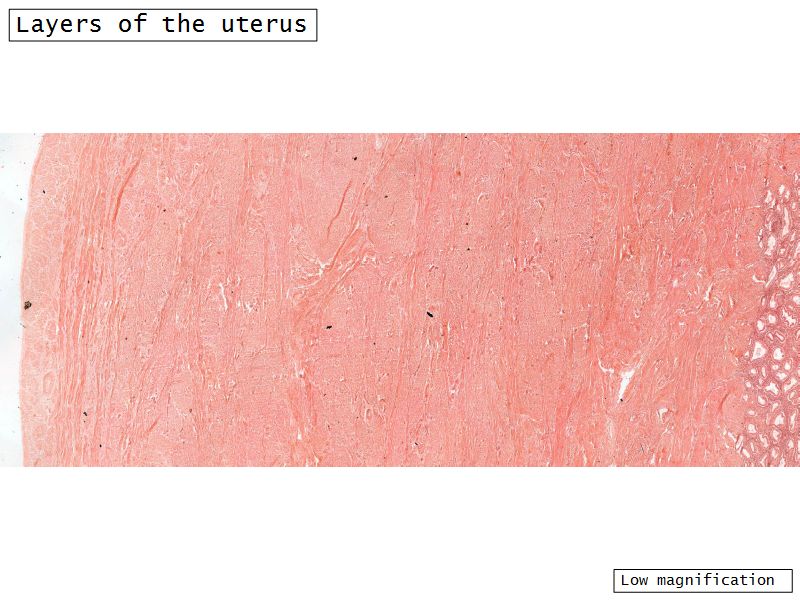

Three layers

- Endometrium

- Formation placenta

- Myometrium

- Enlarge during pregnancy

- Expulsion fetus & placenta

- Adventitia

Myometrium

- Enlarge during pregnancy

- Expulsion fetus & placenta

- 3 layers indistinct smooth

- Inner longitudinal/oblique

- Central circular

- Large blood vessels

- Stratum vasculare

- Outer longitudinal/oblique

Adventitia

- Or serosa

- Covers myometrium